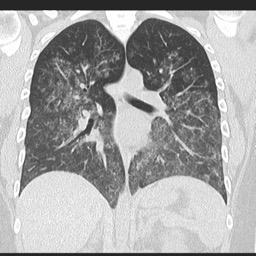

o HRCT: rozlane zmętnienia szklisto-matowe i konsolidacja pęcherzyków płucnych.

Rozlane krwawienie pęcherzykowe spowodowane zapaleniem naczyń

Źródło: radiopaedia.org